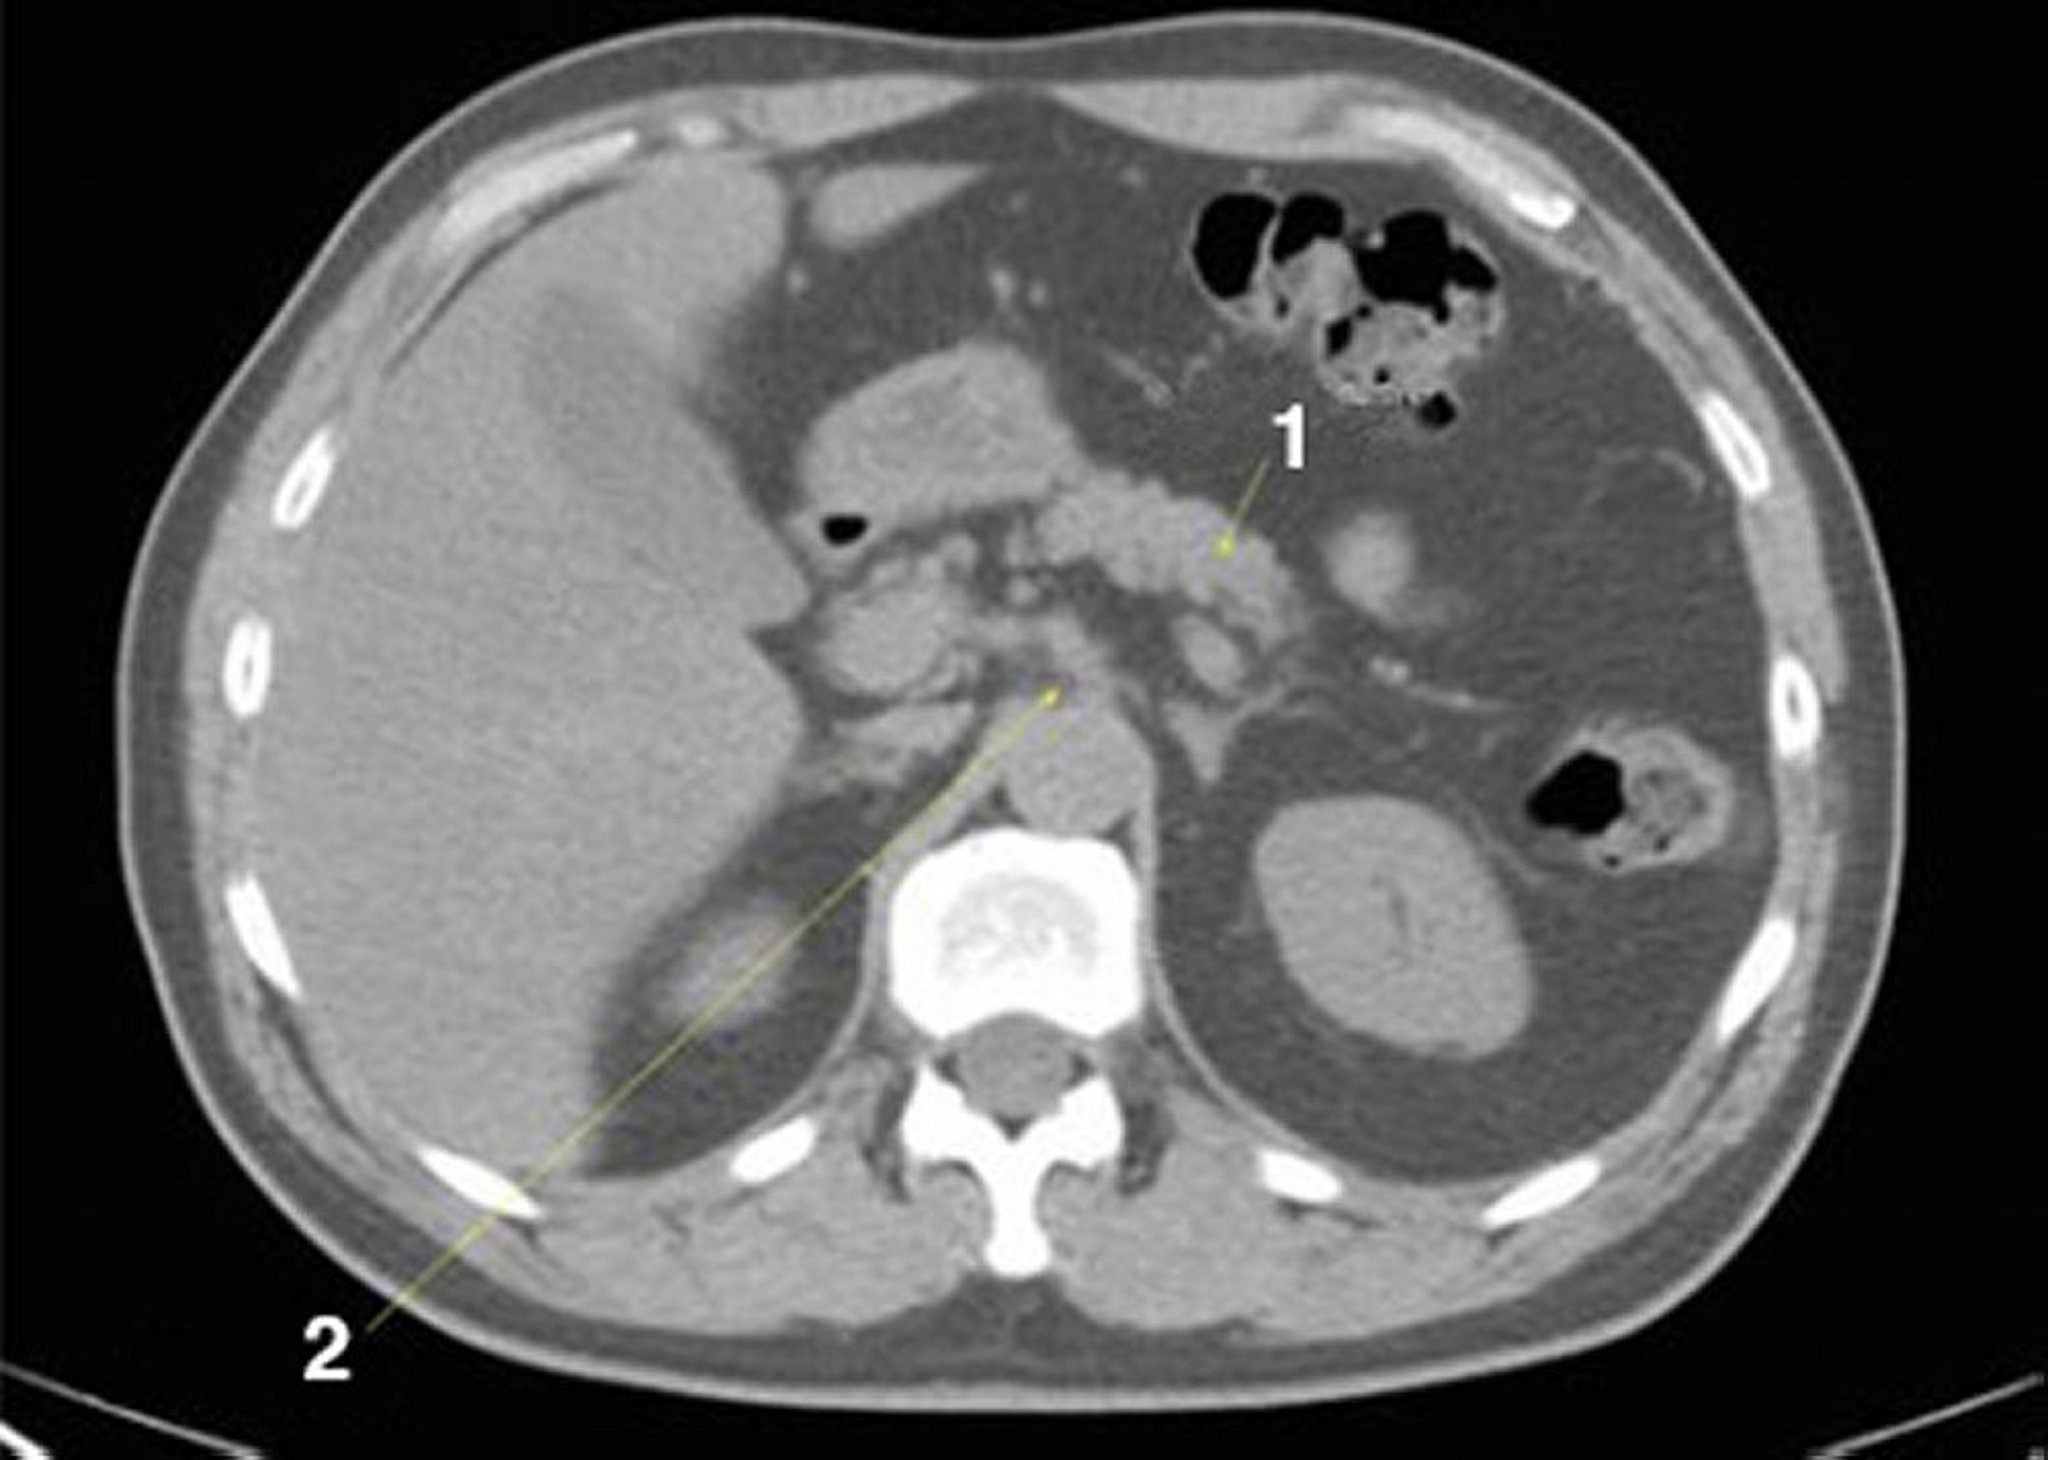

Phim chụp CT vùng bụng và vùng chậu không thuốc cản quang cho thấy giải phẫu bình thường (lát cắt 9)

1 = tụy; 2 = trục celiac.